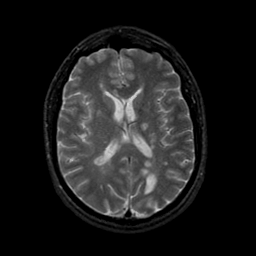

MR Study #9, April 14, 1991 -- Slice #29